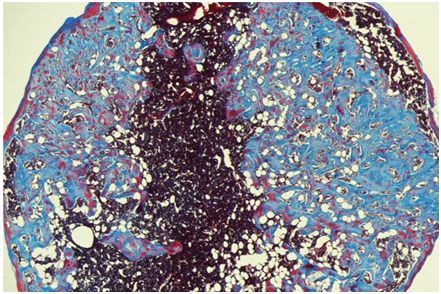

在一項新的研究中,來自美國哈佛大學的研究人員開發(fā)出一種可注射的海綿狀凝膠,可增強骨髓移植后的T細胞產(chǎn)生,從而增加了免疫系統(tǒng)中的這些關鍵組分的數(shù)量和多樣性。這種生物工程支架(即海綿狀凝膠)可在骨髓移植的同時注射到皮膚下,從而有助于在接受移植后恢復免疫系統(tǒng)。相關研究結果發(fā)表在Nature Biotechnology期刊上。

圖片來源:Harvard University

利用Mooney實驗室在用于提供細胞指導性線索的生物材料開發(fā)方面的開拓性研究成果,這些研究人員設計了一種具有允許細胞進出的大孔的海綿狀凝膠。這種凝膠具有兩種內(nèi)置的蛋白:第一種蛋白招募外部細胞,第二種蛋白促進T細胞祖細胞(T-cell progenitor)產(chǎn)生。第一種蛋白稱為骨形態(tài)發(fā)生蛋白2(BMP2),招募局部的細胞并促進它們變成骨細胞。一旦這種凝膠類似于血管化的骨髓,第二種蛋白就促進生活在這種生物工程支架中的造血干細胞產(chǎn)生T細胞祖細胞。

當這些研究人員在接受造血干細胞移植的小鼠中測試這種生物工程支架時,他們發(fā)現(xiàn)相比于沒有接受這種支架注射的小鼠,接受這種注射的小鼠更快地產(chǎn)生T細胞。這些研究人員還發(fā)現(xiàn),在植入這種生物工程支架的小鼠中,移植物抗宿主病的發(fā)生率顯著降低,其中在移植物抗宿主病中,供者細胞攻擊患者的健康組織和器官。接下來,這些研究人員的目標是擴大這項研究的規(guī)模,使得它適用于臨床環(huán)境。